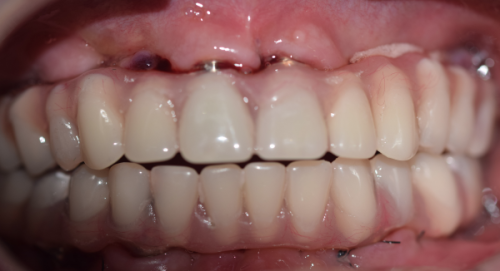

| 半口All - on - 4(韩系) | 39800元起 |

| 全口All - on - 6(瑞士) | 78000元起 |

服务贴心周到:大连米嘉口腔重视患者的就医体验,提供温馨舒适的就诊环境和贴心的服务。从询问、检查、手术到术后跟踪,全程都有专精的医护人员陪伴和指导。而且实行价格透明制度,所有费用均公开透明,无隐性消费。种植牙还提供5年质保,复诊免费,降低患者后期维护成本。